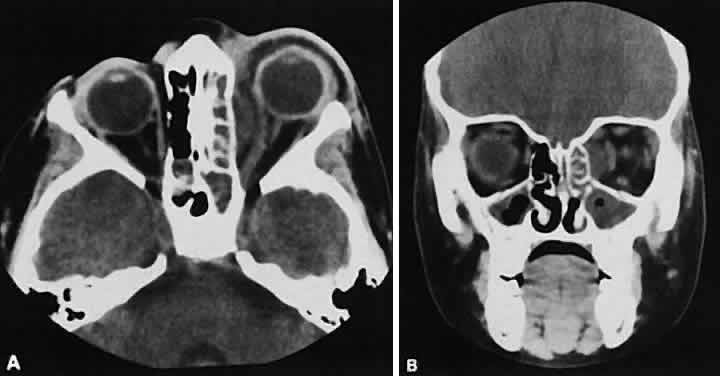

The CT evaluation of orbital myositis may show diffuse irregular enlargement of one or more EOMs; enlargement can be bilateral (Fig. 5). Incontradistinction to Graves' orbitopathy, involvement of the tendinous insertion and edema ofthe adjacent fat may be noted. Other conditions associated with EOM enlargement are listed in Table 2.31–33